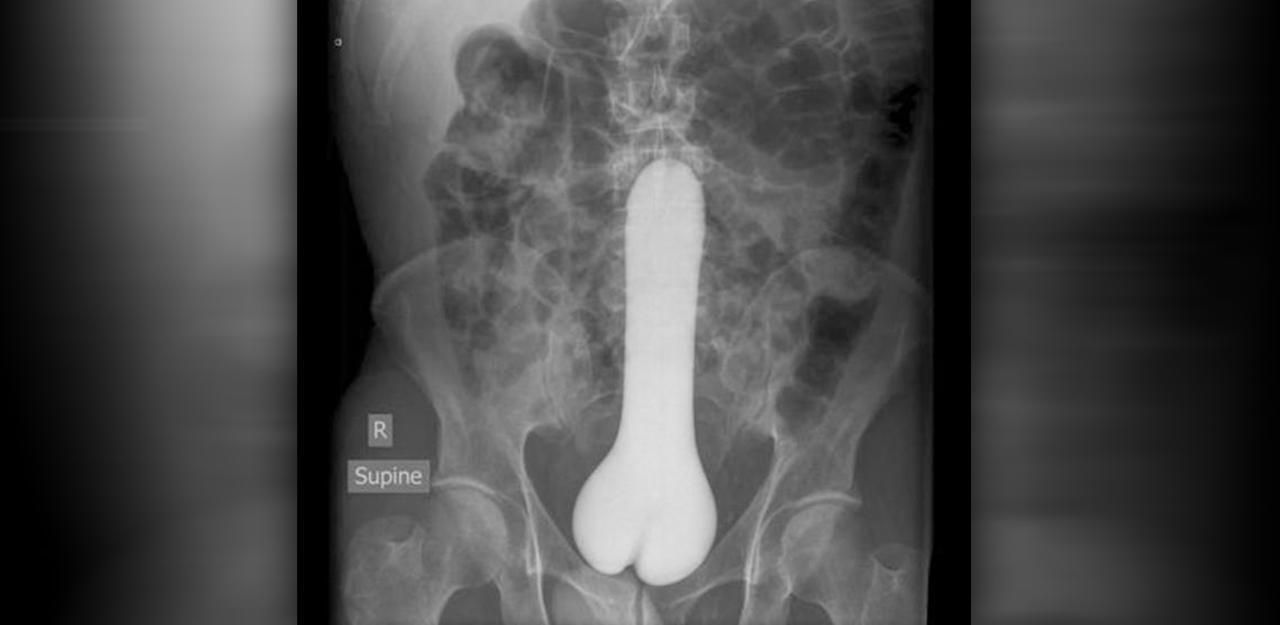

Dieser Kandidat war darauf aus, sich mit einem besonders großen Spielzeug zu vergnügen.

Bild: Radiopeadia.org